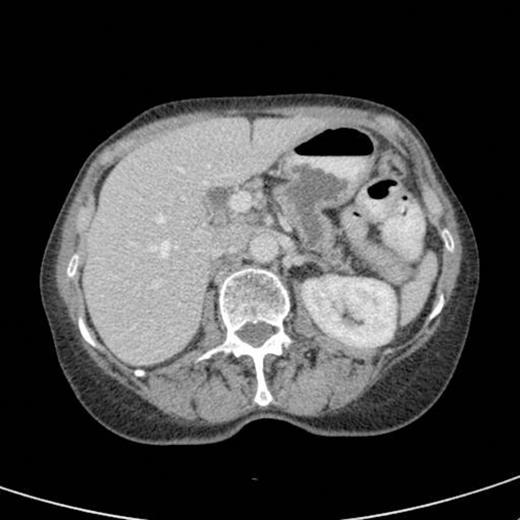

CT scan showing pancreatic duct dilatation to 15 mm with side branch dilatation in uncinate process and atrophic pancreas

CT scan done 2 years later revealed marked dilatation and tortuosity of the main pancreatic duct (12-13mm at the head) with atrophy of the body and tail (Fig1). Repeat scans done on an yearly basis over the next three years reported no progressive change. CT scan done 6 years after the original diagnosis revealed pancreatic duct dilatation to 15 mm with side branch dilatation in uncinate process and atrophic pancreas (Fig 2). A diagnosis of mucinous ductal ectasia or an intraductal papillary mucinous tumour was suggested. On clinical review, patient complained of epigastric discomfort, loose stools, anorexia and weight loss. Upper GI endoscopy and colonoscopy was normal. Faecal elastase was less than 100 confirming pancreatic insufficiency for which she was commenced on creon.